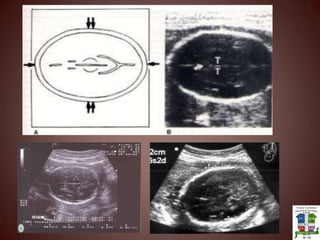

Saco GestacionalEs la primer estructura que aparece ( debe coincidir con 1200mUI subB (ECO TV) y 3600mUI subB (eco Abdominal)Es el primer parámetro ecográfico para determinar Edad Gestacional (DSM)DSM = DL + DT+ DAP / 3MAL PRONOSTICOUBICACIÓN ANORMALCONTORNO IRREGULAR O AUSENCIA DEL DOBLE ANILLOESPESOR DEL TROFOBLASTO MENOR A 2MM

BiometríaParámetros CefálicosDiámetro Biparietal: Se debe ubicar en un plano TRASTALAMICO. El diámetro se toma de tabla interna del parietal distal (con respecto al transductor) a tabla externa del parietal proximalCircunferencia Cefálica: En el  mismo plano (TRASTALAMICO) setoma dos diámetros (DL fronto-occipital Y DAP biparietal) SIMPRE DE TABLA EXTERNA A TABLA EXTERNA.Circunferencia Abdominal: Se realiza un corte axial abdominal donde se observeCámara GástricaVena Umbilical Aorta VCISuprarenal derechaLongitud Femoral:El hueso no se tiene que juntar con el musculo o con la piel debe encontrarse en forma simétrica. No incluir epífisis femoral

Saco GestacionalEs laprimer estructura que aparece ( debe coincidir con 1200mUI subB (ECO TV) y 3600mUI subB (eco Abdominal)Es el primer parámetro ecográfico para determinar Edad Gestacional (DSM)DSM = DL + DT+ DAP / 3MAL PRONOSTICOUBICACIÓN ANORMALCONTORNO IRREGULAR O AUSENCIA DEL DOBLE ANILLOESPESOR DEL TROFOBLASTO MENOR A 2MM

BiometríaParámetros CefálicosDiámetro Biparietal:Se debe ubicar en un plano TRASTALAMICO. El diámetro se toma de tabla interna del parietal distal (con respecto al transductor) a tabla externa del parietal proximalCircunferencia Cefálica: En el mismo plano (TRASTALAMICO) setoma dos diámetros (DL fronto-occipital Y DAP biparietal) SIMPRE DE TABLA EXTERNA A TABLA EXTERNA.Circunferencia Abdominal: Se realiza un corte axial abdominal donde se observeCámara GástricaVena Umbilical Aorta VCISuprarenal derechaLongitud Femoral:El hueso no se tiene que juntar con el musculo o con la piel debe encontrarse en forma simétrica. No incluir epífisis femoral